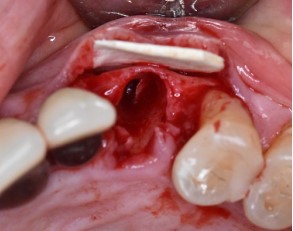

,Dentistry is, in many ways, a pursuit of nature. That’s certainly the case for periodontist Dr. Vinay Bhide, whose mission is to not only replicate the function and esthetics of a patient’s natural teeth, but rebuild the underlying structures that support them. “Any time you can mimic nature, it is a benefit in terms of longevity and predictability,” he shared., ,One way that Dr. Bhide attempts to mimic nature is through guided bone regeneration (GBR). “What we’re trying to do with GBR,” he explained, “is to reconstruct a deficient jawbone to the point where we’re able to put implants into a prosthetically- or functionally oriented position.” This ultimately enables the implant to function properly, while allowing the patient to eat comfortably and enjoy an improved quality of life., , ,

,“I know the places where I can use it, and in those places, I think it works beautifully. It’s a gem of a product.”,– Vinay Bhide, DDS, MSc, FRCD, , ,The goal of GBR, shared Dr. Bhide, is to regain the alveolar bone lost following tooth extraction or periodontal disease, which typically requires filling the treatment site with either allogeneic or xenogeneic bone particles, and then covering it with a membrane made from collagen. “After about 6 months, we reenter the site and hopefully have a nice, rich jawbone that has good dimensions for us to place implants.”, ,Unfortunately, the results of GBR using conventional membranes can be unpredictable. “As long as I’ve been doing this procedure, I haven’t been totally happy with the results that I was achieving,” Dr. Bhide said. “Sometimes I’d see great results, and other times, although I would be able to get implants in, I wouldn’t be fully satisfied.” In turn, he began his search for a solution that would reliably give him a better outcome., ,Last year, Dr. Bhide’s search for the ideal bone grafting material unexpectedly came to an end amid a scene familiar to many dentists—cleaning off a desktop’s worth of promotional materials. Sifting through the pile, he happened to come across a 2-page flyer that “stuck out like a sore thumb.” It described a unique, demineralized cortical allograph sheet material from Implant Direct. It was DirectGen Flex, a product that Dr. Bhide immediately thought could be his “golden ticket” to more predictable and natural bone regeneration., ,Soon after, Dr. Bhide picked up the phone, ordered the product, and got to work. “I started by using it in about 4 or 5 cases and decided to just wait and see what happened. And I was really, really happy with the results I was getting—at that point, the material became a game-changer for me.”, ,In working with DirectGen Flex, Dr. Bhide identified 3 key benefits that make it a game-changing membrane material:,1. Made of 100% demineralized cortical bone, which makes it an optimal replacement for the body’s natural cortical bone layer. “When you’re using demineralized bone, it will actually turn over into new bone because the demineralization process exposes the surface to factors called bone morphogenetic proteins, which are potent inducers of bone formation.”,2. Rigid but with good flexibility, which in his experience, allows clinicians to truly “create and maintain a good contour and dimension of bone without worrying about things collapsing.”,3. Extremely easy to use. After working with the material over the past year, he’s had few issues. “I know the places where I can use it, and in those places, I think it works beautifully. It’s a gem of a product.”, ,To learn more about Implant Direct and speak with a representative, visit implantdirect.com. To see more case examples from Dr. Bhide, find him on Instagram @drbhideperio.,